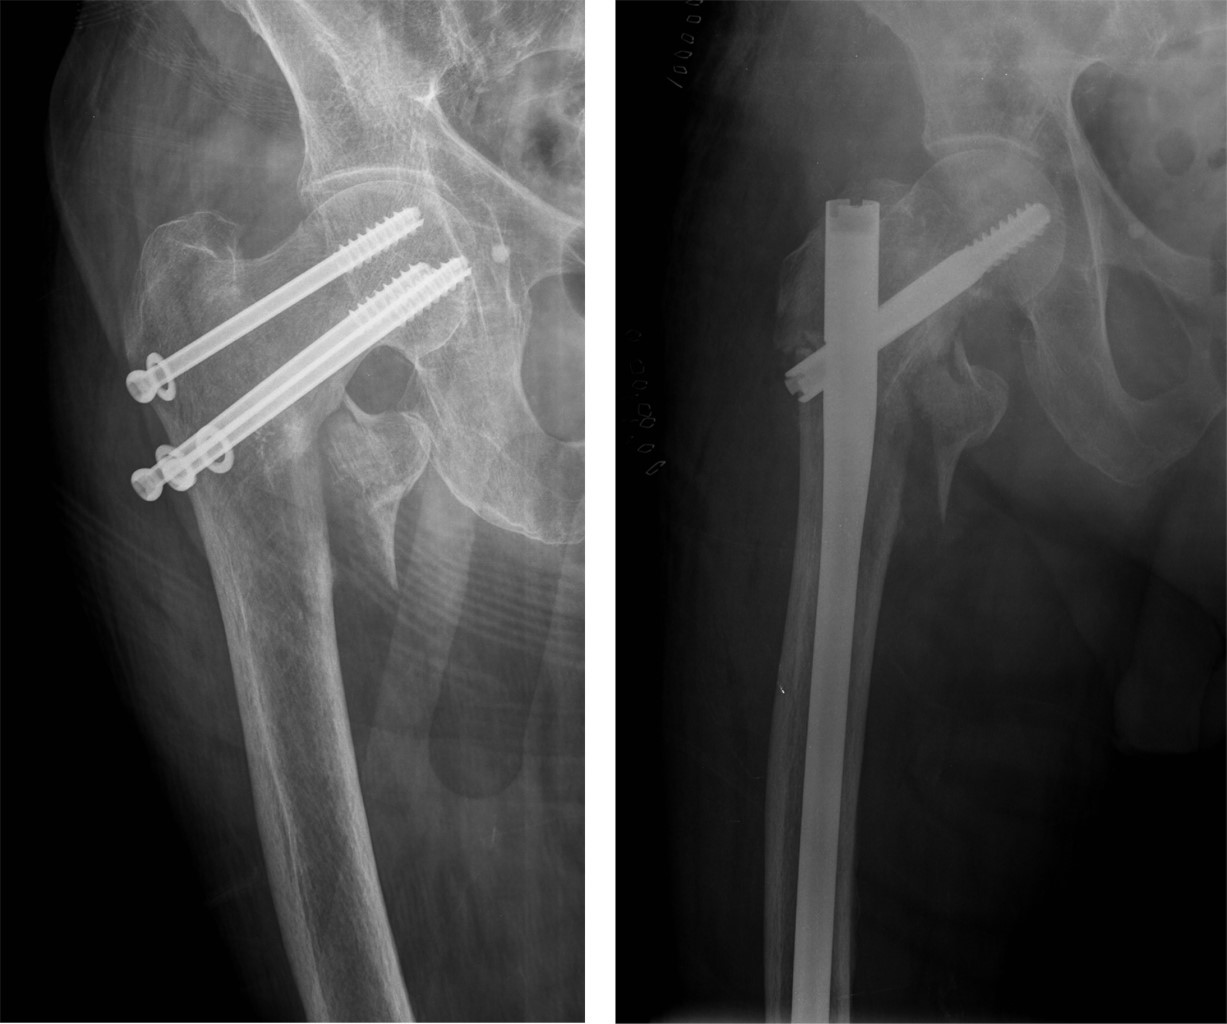

Periosteosynthesis subtrochanteric fractures after fixation of femoral neck fractures with cannulated screws

Introduction: the objective of this study was to analyze the incidence and predisposing factors in subtrochanteric fractures on hips previously treated with cannulated screws after suffering a subcapital fracture, based on eight cases registered in the last 20 years. Material and methods: this is a retrospective observational study on a series of patients with a diagnosis of subtrochanteric hip fracture, who have been treated in recent months for a subcapital fracture of the same hip by osteosynthesis with cannulated screws. The study period was 20 years (2000-2020). Results: of the eight cases, five were women and three were men, with a mean age of 75.12 years (range 59-87 years). In all cases, the subtrochanteric fracture occurred within a year after the first fracture, the time elapsed between the two fractures was four months on average (range 1-9 months). Regarding the disposition of the cannulated screws, most of the 7/8 cases were in the shape of an upper vertex triangle, and only one case was in the shape of an inverted triangle or lower vertex. The entry point into the femoral external cortex was at the level of the lesser trochanter in six cases, and in two cases this entry was distal to the lesser trochanter. Conclusion: in our experience, in the etiology of subtrochanteric fractures, the introduction of screws distal to the lesser trochanter, and the distribution of the screws in a triangular shape are the two main objective predisposing factors.

Figure 1

Figure 2